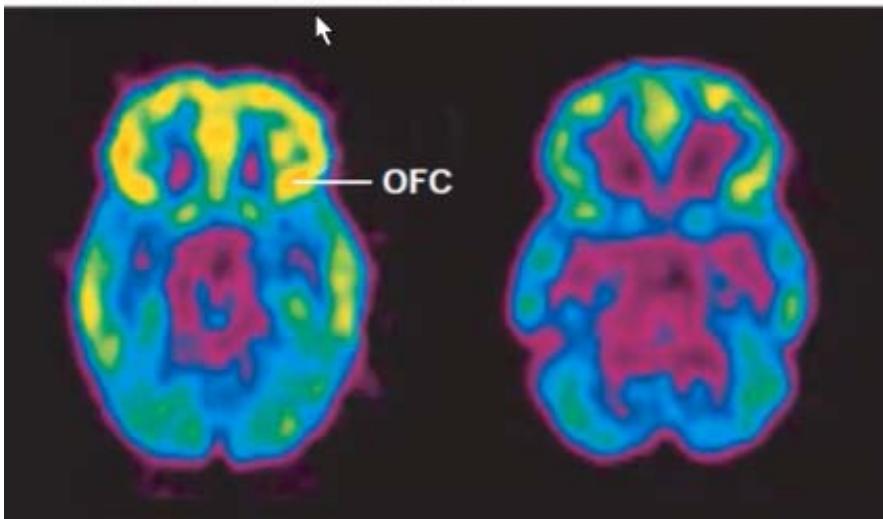

Much of the literature points to neuroadaptations in the various aspects of the PFC as leading to persistent addictive behaviors, including the devaluation of natural rewards, diminished cognitive control, and hyper responsiveness to drug-associated stimuli (Koob, G.andLe Moal, M., 2001; Kalivas and Volkow, 2005; Carelli and West, 2014). Generally, the view continues that changes in the PFC contribute to escalation of substance use through mediating conditioned responses, drug craving, and loss of behavioral control (Feltenstein, M. et al, 2021) In light of our observations of clients with severe substance use disorder over the first 30 to 45 days of recovery (abstinence), neuroimaging studies(Goldstein, R. and Volkow, N., 2011) and additional studies focusing

on the effects of chronic stress and substances on the PFC (Koob, G. and Schulkin, J., 2019), we offer an alternative view which is best observed in recovery.

b Brain glucose metabolism

Figure 8: Harvard Medical School (2021). Understanding Addiction. OFC refers to orbitofrontal cortex

Healthy Control After 2 years cocaine abuse As shown in the scan above, neuroimaging studies reveal an emerging pattern of generalized prefrontal cortex (PFC) dysfunction in drug-addicted individuals. This worsening PFC hypofunction is coincident with more drug use, worse PFC-related task performance and greater likelihood of relapse. Widespread PFC activation is seen in drug-addicted individuals upon taking cocaine or other drugs and upon presentation of drug-related cues. We believe that this is compatible with dopamine surges from the NAc and VTA to the PFC, which then creates a transient focus on obtaining the drug of choice or otherwise. We additionally purport that a degree of PFC dysfunction precedes drug use, creating vulnerability for susceptible persons in developing substance use disorders.